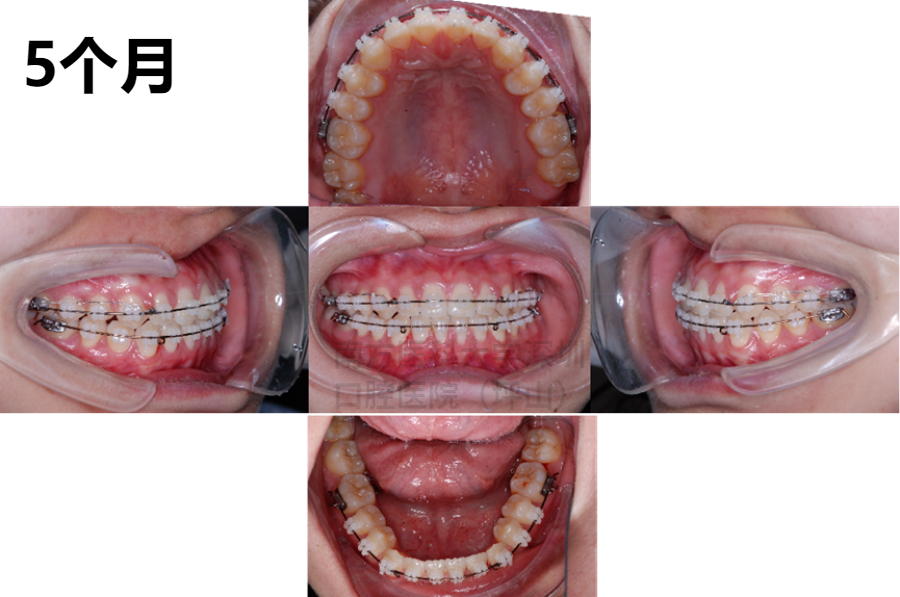

before<<滑动观看矫正过程>>after

一年多的时间,关闭了我的牙齿间隙,咬合关系也得到了改善。在整个正畸的过程中,易医生非常认真负责,人很温柔,超级耐心。